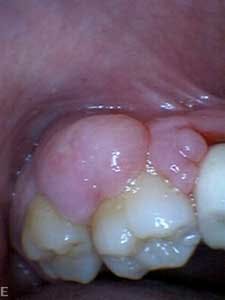

Dental examination revealed gingival swelling and bleeding on probing. Periodontal probing showed moderate-to-deep pocket depths in all posterior teeth (figures 1–3). Generalized bone loss was observed on radiographs (figures 4–6). Tooth vitality and percussion tests were negative. Teeth 2, 3, 31, 14, and 15 had Class III mobility. The patient was diagnosed with Type IV chronic adult periodontitis. Treatment options were discussed, and, after explanation, the patient agreed to the LANAP procedure.

Patient presentation before LANAP treatment (figures 1–6)